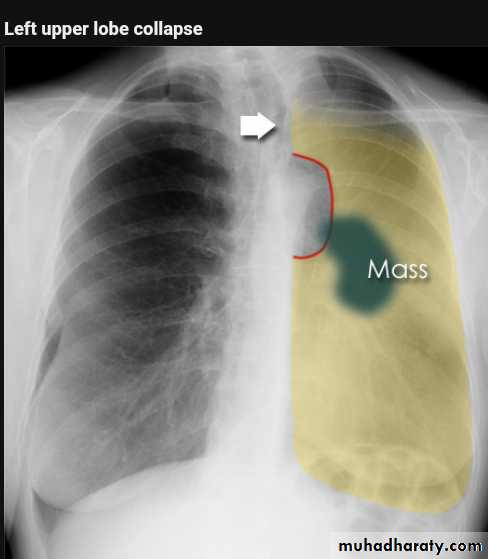

Left upper lobe collapse has distinctive features but can be challenging to identify on chest radiographs by the uninitiated.

Radiographic features

The left upper lobe collapses anteriorly becoming a thin sheet of tissue apposed to the anterior chest wall, and appears as a hazy or veiling opacity extending out from the hilum and fading out inferiorly . It thus reverses the normal slight increase in radiographic density seen as you move down the lung (due to increased thickness of the chest soft tissues).

Parts of the normal cardiomediastinal contour may also be obliterated where the left upper lobe, particularly the lingula abut the left heart border. The anterior parts of the aortic arch are also often obliterated from view.

In some cases the hyperexpanded superior segment of the left lower lobe insinuates itself between the left upper lobe and the superior mediastinum, sharply silhouetting the aortic arch and resulting in a lucency medially. This is known as the luftsichel sign.

The left hilum is also drawn upwards, resulting in an almost horizontal course of the left main bronchus and vertical course of the left lower lobe bronchus.

Non-specific signs indicating left sided atelectasis will also be present, including:

elevation of the hemidiaphragm

'peaked' or 'tented' hemidiaphragm: juxtaphrenic peak sign

crowding of the left sided ribs

shift of the mediastinum to the left

On lateral projections the left lower lobe is hyperexpanded and the oblique fissure displaced anteriorly. There is associated increase in the retrosternal opacity.